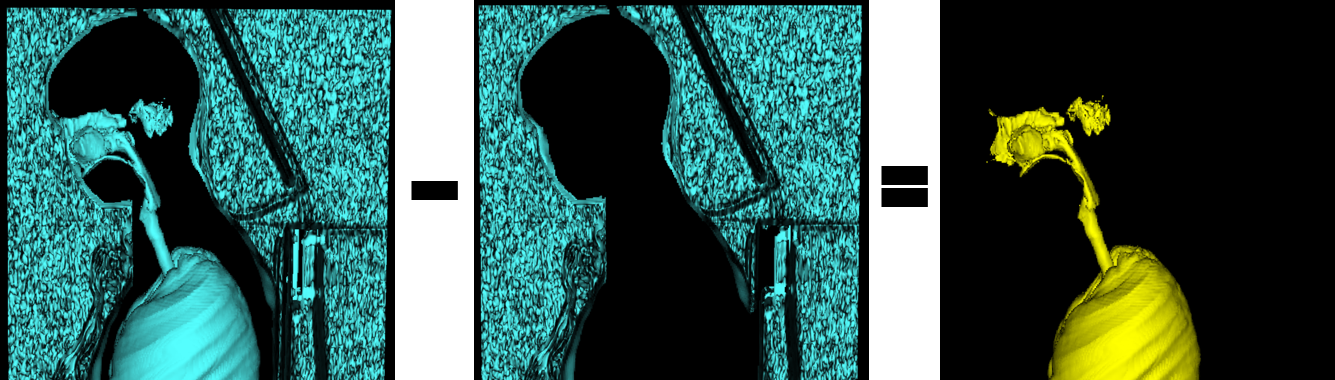

Для выделения внутреннего воздуха тела удалим все объекты, которые прилегают к углам воксельной сцены. Таким образом избавимся от внешнего воздуха.

Однако, не во всех случаях будет удалён воздух внутри стола томографа, так как он может не иметь связи с углами сцены.

Поэтому просканируем не только углы, но и все воксели, лежащие на любой из краевых плоскостей сцены. Но в результате почему-то удалились и сами лёгкие. Оказывается, трахея тоже имела связь с верхней плоскостью сцены.

Придётся исключить верхнюю плоскость из зоны сканирования. Также бывают исследования, в которых лёгкие были захвачены не полностью и нижняя плоскость имеет связь с легкими. Так что при желании можно исключить и нижнюю плоскость.

Но такой метод действует только на грудных исследованиях. В случае же захвата полного объёма тела на снимке появится связь внутреннего и внешнего воздуха через носовую полость. Поэтому необходимо применить морфологическую эрозию для разделения внутреннего и внешнего воздуха.

После применения эрозии можем вернуться к полученному ранее методу сегментации внешнего воздуха по признаку соседства с боковыми плоскостями сцены.

Выделив внешний воздух, можно было бы сразу отнять его из общего объёма воздуха и лёгких и получить внутренний воздух тела и легкие. Но есть одна проблема. После эрозии была потеряна часть информации о внешнем воздухе. Чтобы восстановить её, применим дилатацию внешнего воздуха.

Далее вычитаем внешний воздух из всего воздуха и дыхательных органов и получаем внутренний воздух и дыхательные органы.